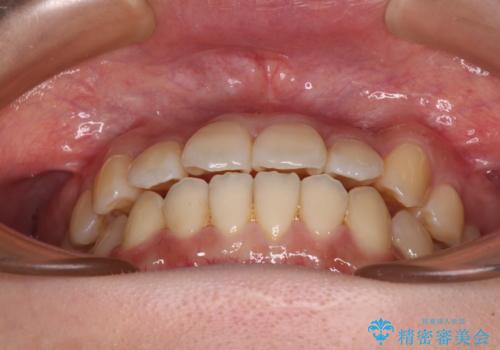

- 八重歯や前歯の捻転とクロスバイトが気になり、インビザラインによる矯正治療を希望して来院された患者様です。

上顎側切歯(上の真ん中から2番目の歯)が舌側転位している場合、無理して動かそうとすると歯髄壊死を起こすリスクが高い印象があります。

インビザライン単体でも治療は可能ですが、安全策としてインビザラインで歯列を移動する前に上顎前歯をワイヤー矯正で整え、その後上下歯列をインビザラインにて矯正治療を行うこととしました。